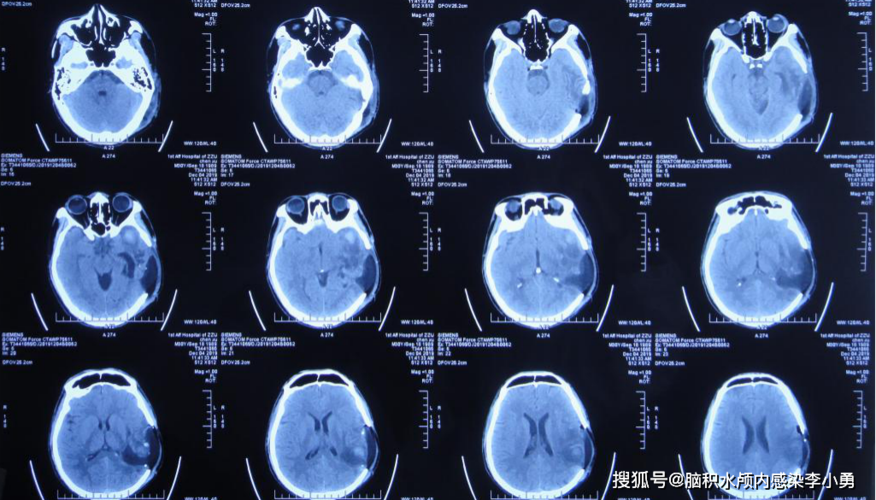

影像总结头颅ct基本知识与常见病变

脑部ct照片真实

头颅CT图片